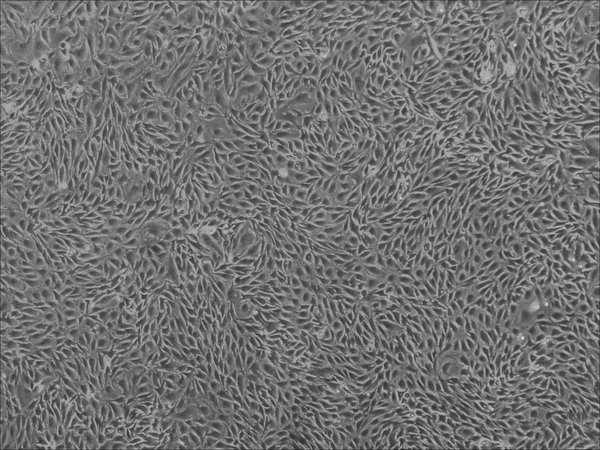

Human Retinal Microvascular Endothelial Cells

| Artikelname: | Human Retinal Microvascular Endothelial Cells |